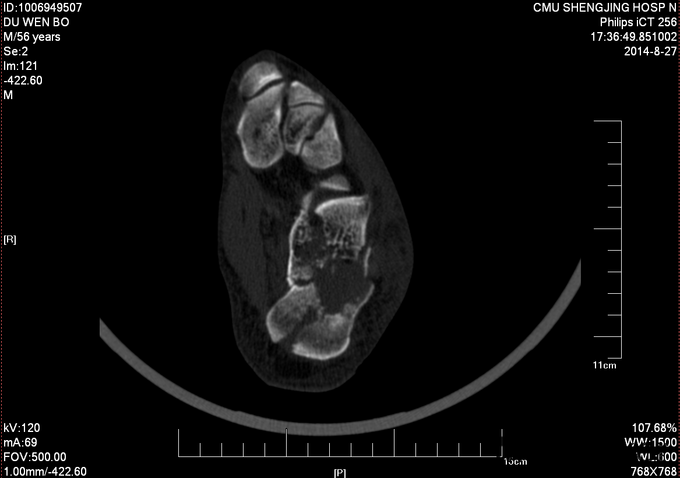

左跟骨骨折sanders2型

患者及其家属自述于2015-10-17 13:30 因在自家干活时不慎从2米高梯子上摔下,当时患者意识清醒,无法站立,左踝部疼痛、肿胀、活动受限,以“左踝部骨折”为诊断收入我科;患者伤来无发热、无头晕、恶心呕吐,无呼吸困难,既往饮食睡眠可,大小便正常; 左踝部肿胀明显,压痛阳性,左踝部活动受限,可闻及骨擦音及骨擦感;患肢皮肤感觉较健侧无明显异常,足趾可活动,足背动脉可触及;